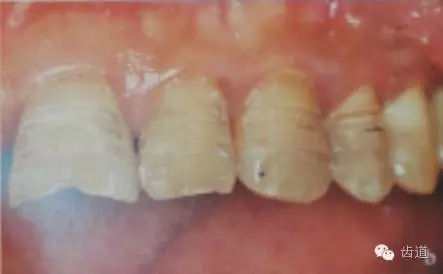

1、唇面預備:先用定深車針定出定深溝,再換合適車針磨除剩余的釉質。

唇面磨除的量依據所用貼面材料及牙齒的變色程度而定。

3、切緣預備:瓷貼面的三種類型不同就是切端預備形態(tài)的不同:

1)開窗型:保持切端完整,沿切緣上緣制備出邊緣;

2)對接型:將患牙切端均勻去除0.5-1.0mm;

3)包繞型:在對接型的基礎上再于切端舌腭側制備并形成0.5-1.0mm深的無角肩臺。